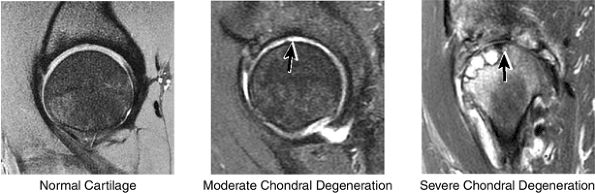

FIGURE 3.32 / Hip Cartilage.